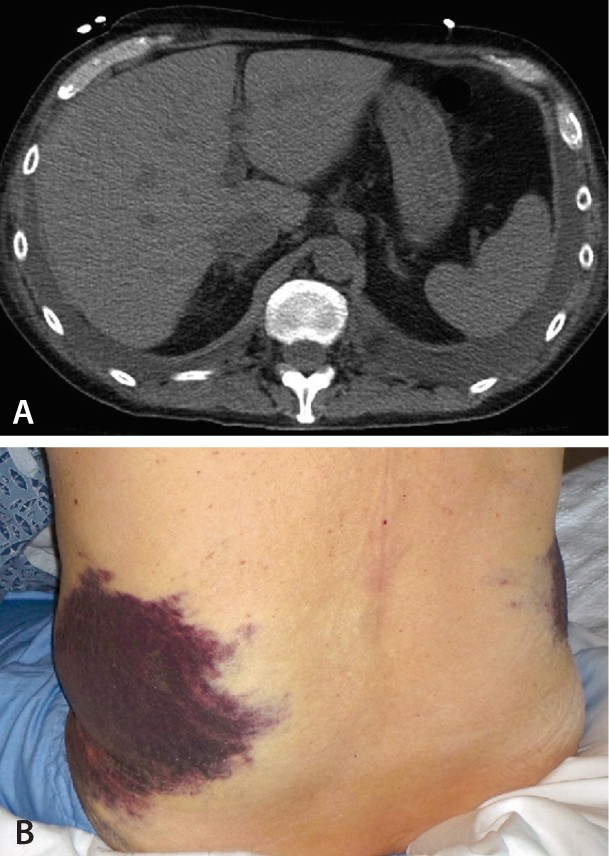

Grey-Turners sign ist wie auch das Cullen-Zeichen ein klinisches Zeichen für eine schwere akute PankreatitisDabei treten im Flankenbereich bläulich. Das Grey-Turner-Zeichen ist wie auch das Cullen-Zeichen ein klinisches Zeichen für eine schwere akute Pankreatitis. Das Zeichen entsteht durch eine Ansammlung von Blut im an das.

This category contains only the following file. Wetter and others published Grey-Turner-Zeichen bei nekrotisierender Pankreatitis Find read and cite all the research you need on. Das Grey-Turner-Zeichen ist ein im Rahmen einer akuten Pankreatitis auftretendes klinisches Zeichen.

Ct Untersuchung Bei Turner Und Cullen Zeichen Der Akuten Pankreatitis